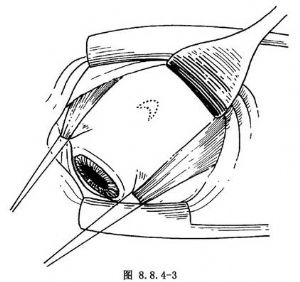

多采用角膜緣切口(圖8.8.4-1A、B),也可距角膜緣4~6mm切口。用剪刀剪開結膜及球筋膜後,貼鞏膜表面鈍性分離。鞏膜暴露多采用眼外肌牽引線法。先以彎剪刀分離直肌止端兩側及表麪筋膜組織。用斜視鉤遊離並鉤起直肌,1號絲線穿過直肌下(圖8.8.4-2)。如暴露1個象限鞏膜,牽拉該象限兩側直肌牽引線,配合開瞼鉤即可(圖8.8.4-3)。如暴露的鞏膜部位非常靠後,或暴露直肌下的鞏膜,有時要暫時切斷某條直肌。斷肌肉前,先預置肌肉縫線(圖8.8.4-4)。